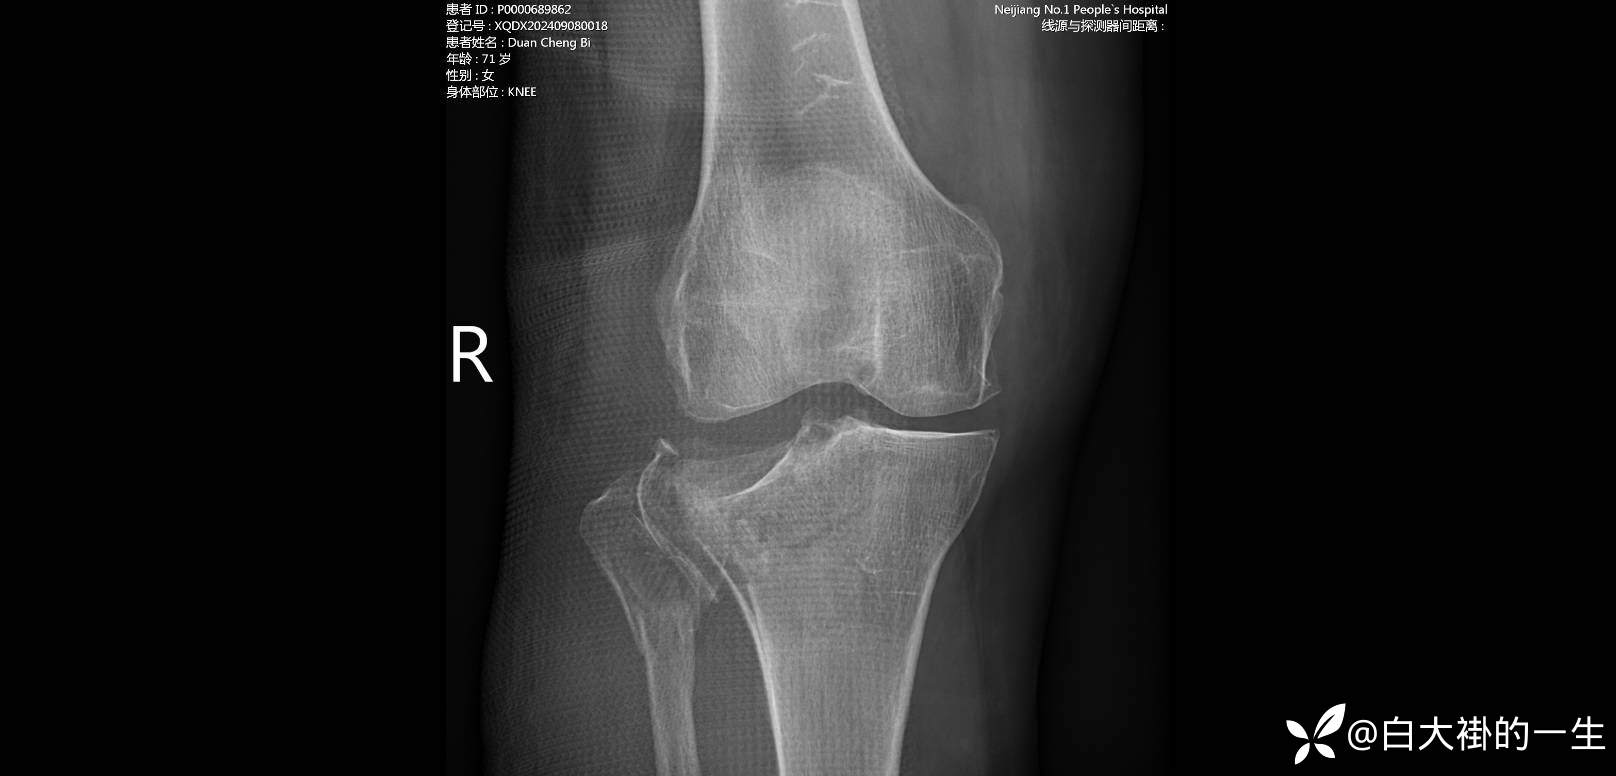

【患者信息】:患者及家属诉于4小时前在过斑马线时被小汽车撞倒,即感右侧膝部疼痛伴活动受限,伴有轻微皮肤擦伤,伴右侧肩部及右侧骨盆处疼痛,伤后患者无昏迷,能回忆起当时情形,伤后略感头晕、头痛,无恶心、呕吐,有胸闷不适,无胸痛,无呼吸困难,无腹胀、腹痛,无大小便失禁等伴随症状。患者遂在亲属陪同下由120救护车送至我院急诊科,急诊行CT检查示:“右胫、腓骨上段粉碎性骨折,右膝、右小腿软组织肿胀,右膝关节腔及髌上囊、右股骨下段内侧旁积液、积血”。急诊以“右侧胫骨平台骨折,右侧腓骨上段粉碎性骨折”收住我科住院治疗。

【检查】:2024-9-7我院急诊行检查提示“1.右胫、腓骨上段粉碎性骨折,右膝、右小腿软组织肿胀,右膝关节腔及髌上囊、右股骨下段内侧旁积液、积血。2. 右膝关节退行性变。3. 头颅CT扫描颅内未见血肿及确切挫裂伤,请随诊。4. 双侧眼球突出;多组副鼻窦炎。5. 双肺上叶数个结节,提示低危结节,请年度随诊。6. 右肺上叶前段含气囊腔。7. 双肾结石;双肾囊肿;双肾盂、输尿管腹段轻度扩张。8. 双侧卵巢囊性病变。9. 盆腔少量积液。1. 右胫、腓骨上段粉碎性骨折,右膝、右小腿软组织肿胀,右膝关节腔及髌上囊、右股骨下段内侧旁”

影像如图:

【临床诊断】:1.右侧胫骨平台粉碎性骨折 2.右侧腓骨上段粉碎性骨折

3.右膝关节退行性变 4.双肾结石